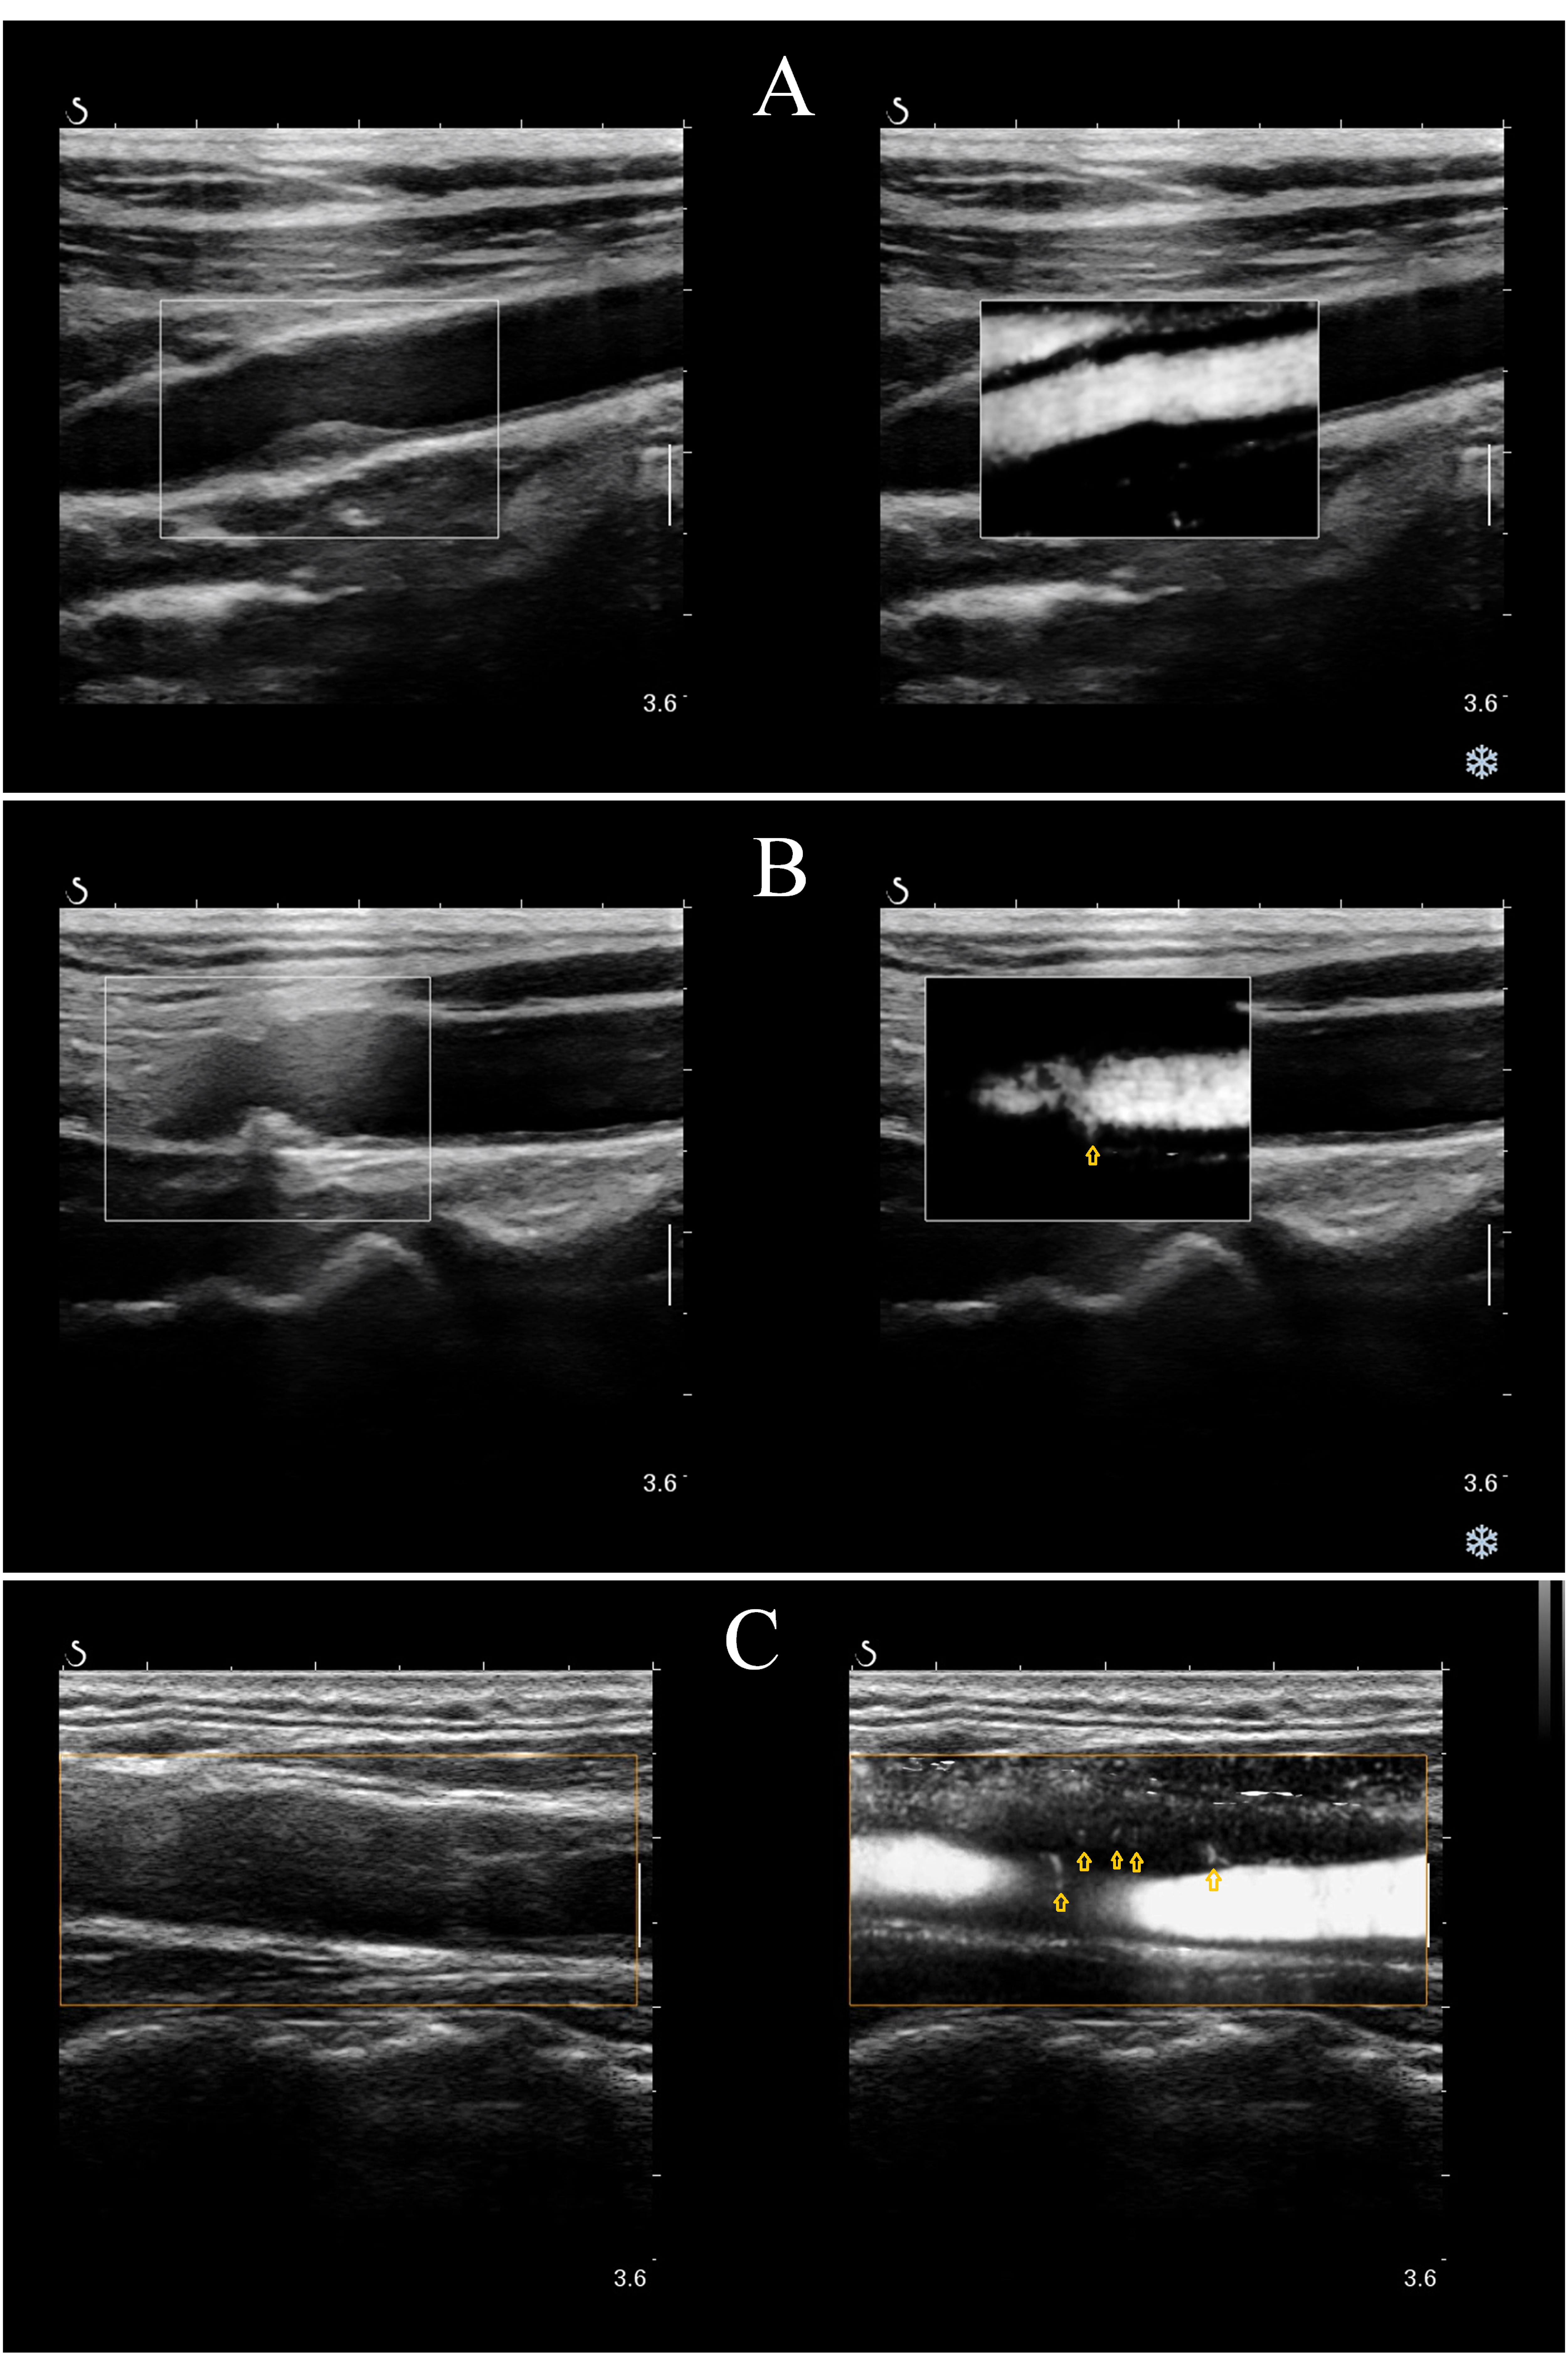

Intraplaque neovascularization (IPN) correlates significantly with plaque vulnerability and can be detected using Angio PLanewave UltraSensitive imaging technology (Angio PL.U.S.; AP). Several immune–inflammatory biomarkers that reflect the state of inflammation and immune homeostasis in the body are currently used to assess cardiovascular and cerebrovascular diseases. This study aimed to investigate the correlation between carotid IPN scores and several immune–inflammatory indicators in patients with different degrees of coronary artery stenosis.

This study prospectively enrolled 107 patients with coronary artery stenosis confirmed by coronary angiography (CAG). Preoperative ultrasonography was performed to screen for carotid plaques, and AP was conducted to determine whether IPN was present and correctly scored. The levels of immune–inflammatory indicators, plaques, and coronary artery lesions between groups with and without IPN and different IPN scores were analyzed. We utilized logistic regression models to determine the independent predictors of IPN and constructed receiver operating characteristic (ROC) curves. Odds ratios (ORs) and 95% confidence intervals (CIs) were calculated.